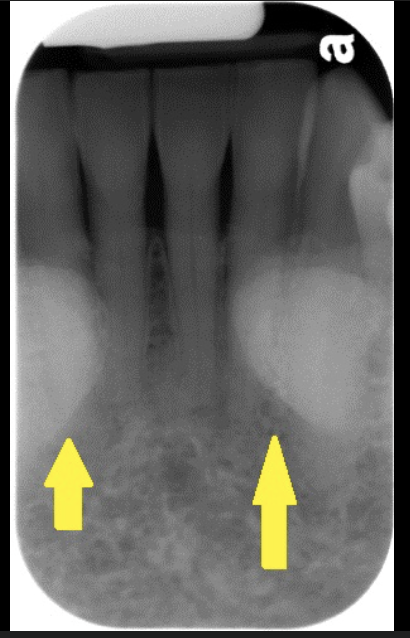

How does the incisive foramen present in a radiograph?

It is a radiolucency that presents between the roots of the maxillary centrals. It is variable in shape, size, and border.

How does the median palatine suture present in a radiograph?

A thin radiolucent line that runs directly between the maxillary incisors.